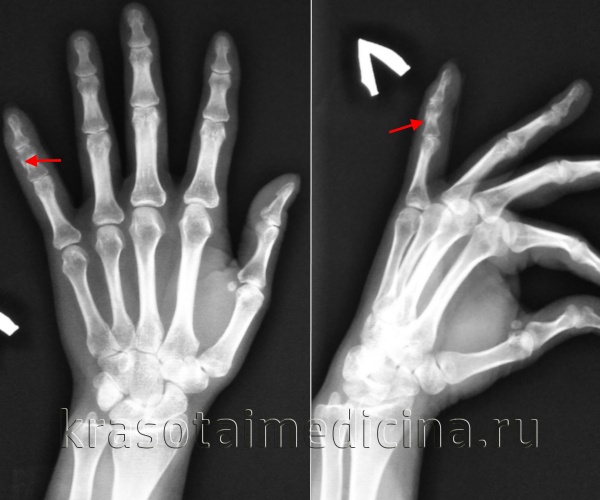

Перелом пальца

Перелом пальца – это нарушение целостности дистальной, средней или основной фаланги пальца руки или ноги в результате травмы. Является широко распространенным повреждением. Может возникать в результате как прямого, так и непрямого травматического воздействия: удара, падения тяжелого предмета, резкого выворачивания и т. д. Проявляется резкой болью, припухлостью, синюшностью и ограничением движений. В ряде случаев наблюдается крепитация и патологическая подвижность. Диагноз уточняют при помощи рентгенографии. Лечение обычно консервативное, в отдельных случаях требуется операция.

Перелом пальца – очень распространенное травматическое повреждение, что обусловлено как высокой активностью, так и тонкостью и недостаточной прочностью дистальных отделов верхних и нижних конечностей по сравнению с остальными сегментами. Чаще возникает при прямой травме, реже образуется вследствие непрямого воздействия (скручивания или переразгибания). Обычно образуется в результате бытовой, производственной или спортивной травмы.

Симптомы перелома пальца

В момент повреждения возникает резкая боль взрывного характера. Палец отечен, возможна синюшность или багровый оттенок кожи. Нередко обнаруживаются кровоизлияния под ноготь или под кожу. При смещении фрагментов выявляется деформация и укорочение сегмента. При открытых повреждениях в ране могут быть видны осколки кости. Движения затруднены. Осевая нагрузка болезненна, может определяться крепитация и патологическая подвижность. Функции конечности грубо нарушаются: при повреждении пальца руки пациент не может использовать пострадавший сегмент для захвата предметов и других простых действий, при травме пальца ноги ограничивается опора.

Диагностика

Диагностический поиск осуществляет врач-травматолог. При повреждении верхней конечности диагноз уточняют при помощи рентгенографии пальцев кисти. Снимки выполняют в двух проекциях, с захватом соседних суставов. Для уточнения харатера повреждения при травмах нижней конечности проводят рентгенографию пальцев стопы.